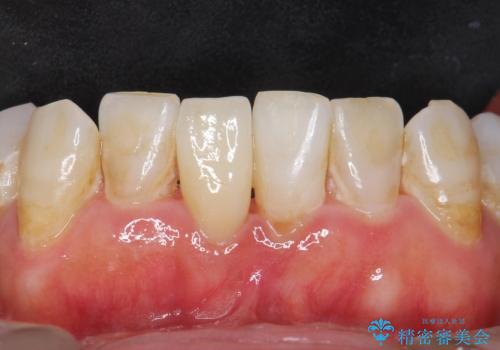

口腔内を精査したところ、右上のブリッジの内側(口蓋側)がかけており、下の前歯(右下1)には唇舌側に瘻孔を伴う大きな根尖病変ができていました。

右上のブリッジ(右上④3②)のやりかえと、下の前歯(右下1)の根管治療を行った後セラミッククラウンによる補綴治療を行いました。

ブリッジとクラウンの自然な仕上がりと咬み心地に喜んで下さいました。

精密な根管治療により、下の前歯の歯ぐきにできていた瘻孔もなくなりました。